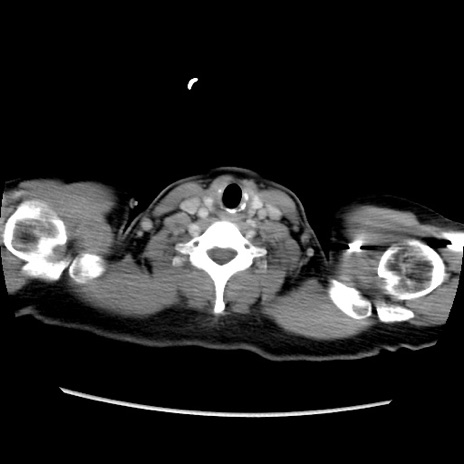

症例39(横断像)

【症例】40歳代女性

【主訴】上下腹部痛

【現病歴】2日目から下腹部痛あり。夜間は痛みで眠れなかった。昨日より上腹部痛と下痢が出現。臥位で痛みは軽快したため、休んでいた。本日になって臥位でも立位でも痛みが強くなってきたため救急要請。

【既往歴】子宮内膜症

【身体所見】部:平坦・軟、左上下腹部に圧痛あり、反跳痛あり。

【データ】WBC 21800、CRP 26.78